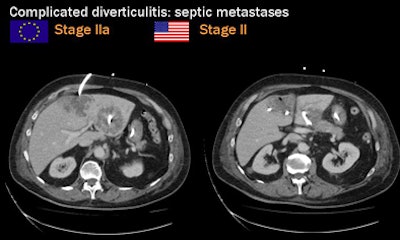

Two staging methods are in widespread use: the Hanson/Stock staging method popular in Europe and the modified Hinchey (Wasvary) technique dominant in the U.S., Rogalla said.

| Two staging methods are in widespread use: the Hanson/Stock staging method popular in Europe and the modified Hinchey dominant in the U.S. All images courtesy of Dr. Patrick Rogalla. |

"Once we have distant metastatic [infection] sites, it will be stage II according to the Hinchey classification, although the local findings are minimal," Rogalla said. "When we see abscess formation, sometimes the sigmoid colon looks almost normal, but in almost all cases that's the source of the infection." Once again the abscesses can be drained at CT-guided fluoroscopy, he said.